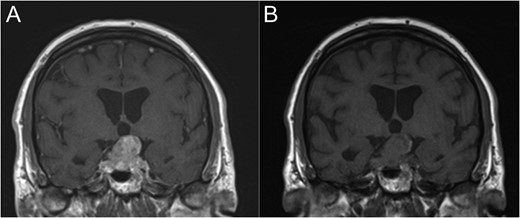

Coronal T1-weighted MRI with (A) and without (B) Gadolinium contrast enhancement.

An 80-year-old man presented with rapid onset visual loss predominantly affecting his left eye. He presented 5 years prior to this with a progressive deterioration in vision associated with a pituitary tumour and at that time underwent endoscopic transphenoidal surgery; however, an incomplete resection was achieved. The original histology confirmed the tumour to be a benign pituitary adenoma. Post-operatively, his vision improved initially and he was managed by the endocrinology team for hypopituitarism. At follow-up, visual field testing and MR scanning showed that the residual tumour was clinically and radiologically stable. His pituitary ademona was considered stable for 5 years until he re-presented.

By far the most likely diagnosis at representation would be a recurrence of the original adenoma. If malignancy elsewhere was known, then a metastasis may have been considered. Given this was a de novo presentation of metastatic lung carcinoma, the diagnosis was something of a surprise.